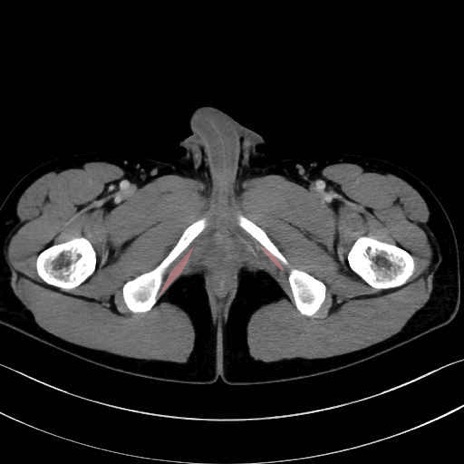

内閉鎖筋 (Obturator internus)